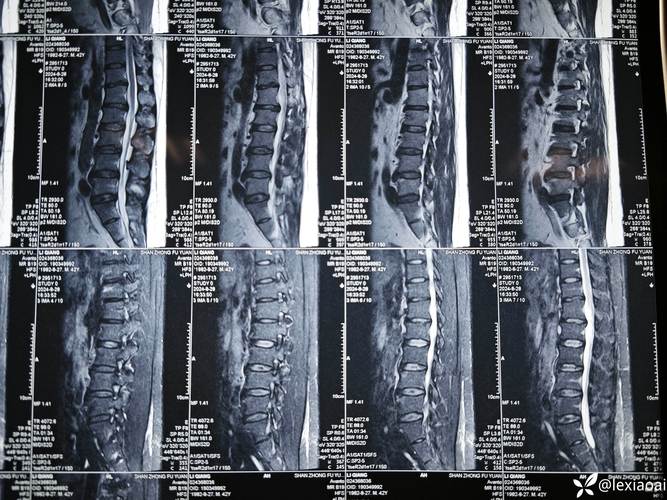

当您或您的医生提到“风湿性脊柱炎要做核磁共振”时,实际上指的是为强直性脊柱炎患者进行MRI检查。

在强直性脊柱炎的MRI报告中,医生主要会寻找以下几种特征性的改变:

- MRI表现:在T1加权像(T1WI)上表现为低信号,在T2加权像(T2WI)或短时反转恢复序列(STIR)上表现为高信号。

核磁共振检查的序列

为了全面评估,强直性脊柱炎的MRI检查通常会包含以下序列:

- T1加权像 (T1WI):主要看解剖结构,如骨头、脂肪、韧带,能清晰显示骨侵蚀、脂肪沉积和骨化。

- T2加权像 (T2WI):主要看液体,如关节积液、囊肿。

- STIR或脂肪抑制序列:这是评估炎症最重要的序列! 它能抑制掉脂肪的高信号,使得有炎症(水肿)的区域信号更加突出,呈明显高信号,大大提高了对骨髓水肿和滑膜炎的检出率。